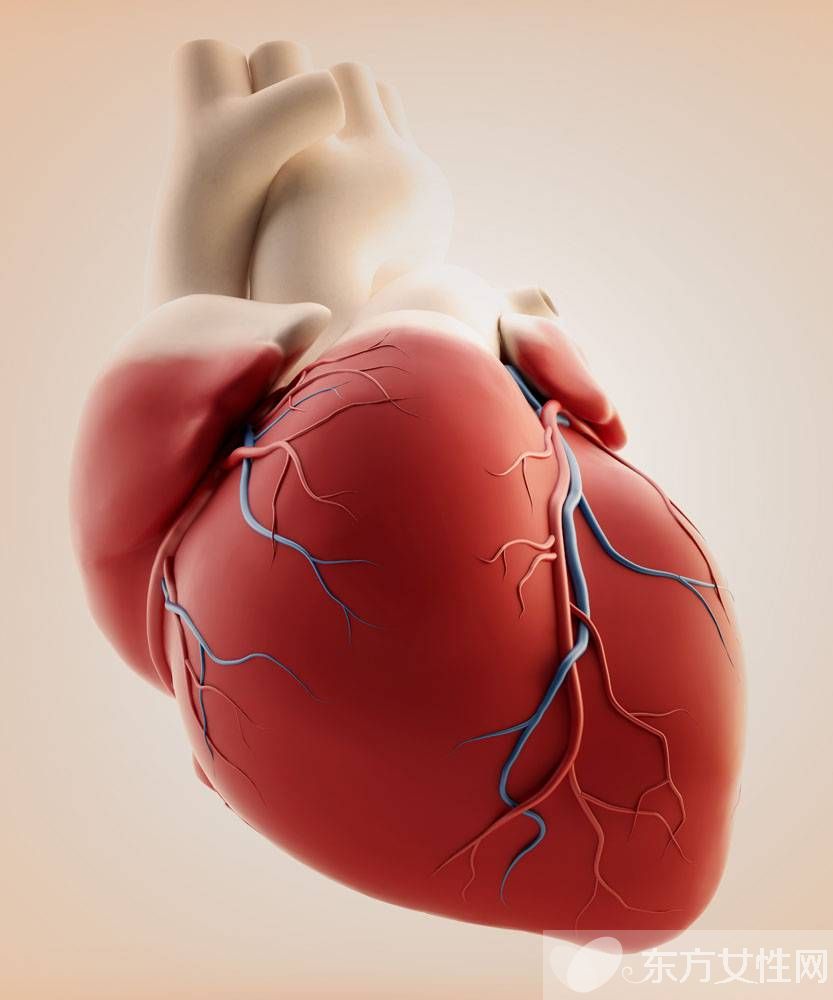

心肌供血不足:心脏活动需要充足的能量供给。心脏本身的供血,有两个显著的特点:

1 心脏的重量虽不足全身体重的1%,但却需要全身血液量的20%才能满足心脏自身的供血;

2 人体为了满足心脏供血的特殊需要,还自成一个供血系统,以保证充足供血。心脏自成的供血系统,是冠状动脉循环。

心肌最怕缺血,缺血就会缺氧。心肌缺血主要由于血液所含物质的变化和血管腔内产生病理改变的结果。大多起因于膳食不合理、运动过少等生活因素导致的高脂血症、高胆固醇血症。血液中的胆固醇,分为高密度脂蛋白胆固醇(简称高密醇)和低密度脂蛋白胆固醇(简称低密醇)。低密醇在血液中,除了供给细胞需要外,多余的那些就会沉积在动脉血管内壁,使血管内壁从不光滑改变开始,直至形成粥样斑块,造成血管通道变得狭窄,甚至阻塞。因此,低密醇属于伤害性胆固醇。而高密醇则会将血液中的胆固醇带到肝脏,进行转化,然后经胆囊入肠道排出体外,属于保护性胆固醇。